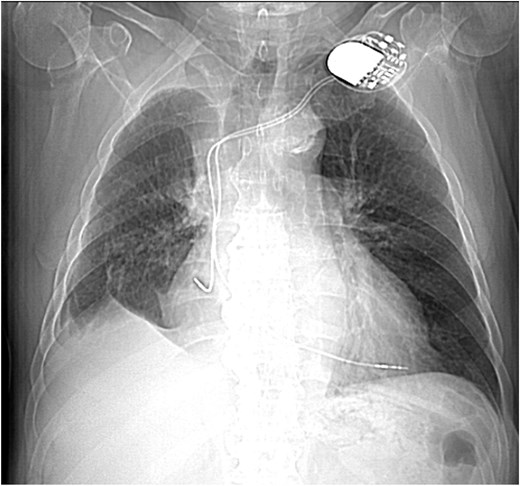

This 78-year-old man initially presented with a chest infection in October 2024, where a chest X-Ray (CXR) showed right upper lobe (RUL) consolidation accompanied by a pleural effusion (Fig. 1). He had no other symptoms, including haemoptysis, shortness of breath, fever, anorexia, or weight loss. A follow-up computed tomography (CT) chest 6 weeks later revealed a large endobronchial lesion in the right main bronchus, resulting in consolidation and partial collapse of the RUL (Figs 2 and 3). He went on to have a positron emission tomography (PET) scan (Fig. 4), CT head, bronchoscopy, and endobronchial ultrasound (EBUS). Imaging revealed a 3.8 cm lesion in the right upper lobe bronchus, which was mostly occluded. The biopsies showed evidence of a myoepithelial carcinoma, a rare pulmonary neoplasm.

CXR showing right upper lobe consolidation with a small right pleural effusion (dual lead pacemaker noted).